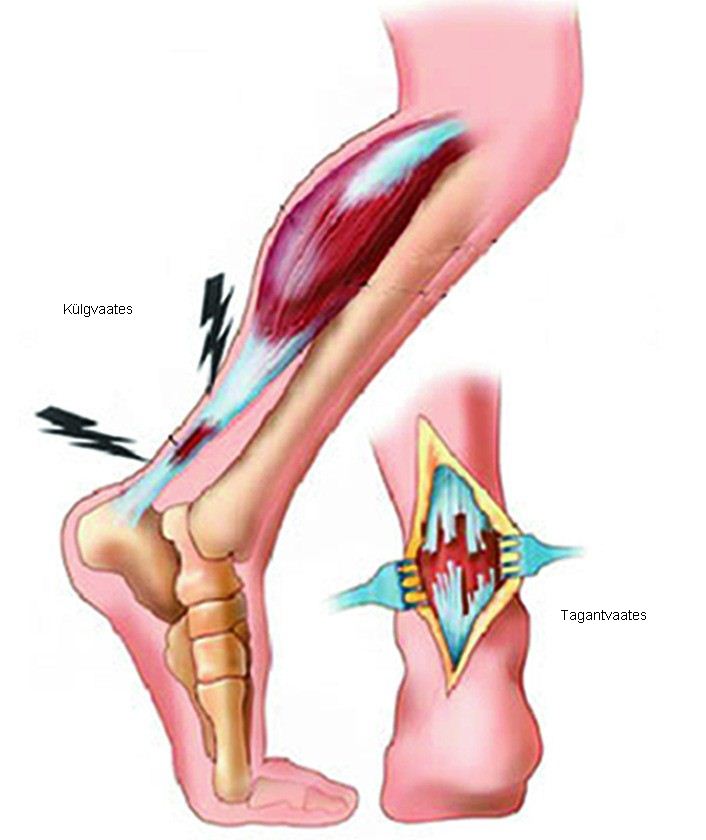

Тендинит Ахиллова сухожилия: симптомы и лечение

Раздел: Картинки на заметку